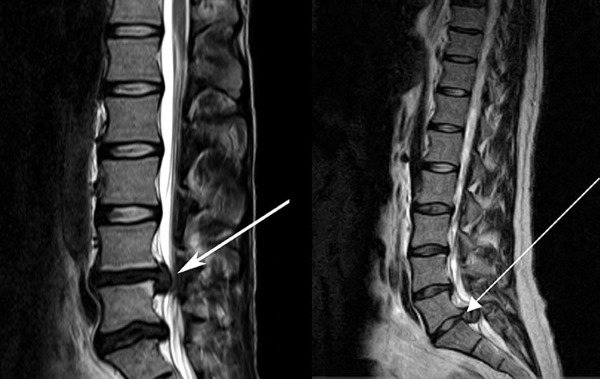

Видео: «МРТ-сканы поясничной грыжи»

- магнитно-резонансная томография (МРТ). Характеризуется как наиболее информативный метод диагностики грыжи: определяет не только деструктивные процессы, размер грыжи, ее расположение и структуру, но также выявляется степень повреждения и защемления нервных окончаний, компрессия корешков позвонков, патологии в структуре околодисковых тканей;